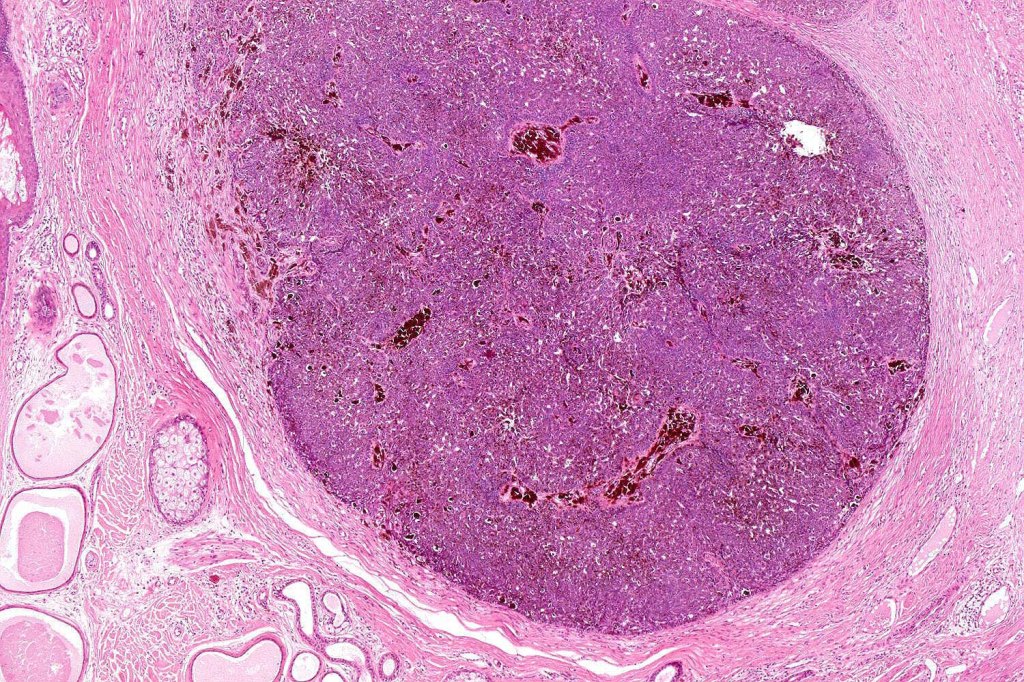

•Sharply circumscribed, unencapsulated nodule in deep dermis +/- subcutaneous fat or deeper (trichoepithelioma is much more superficial)

•Variably sized but generally large, basophilic tumor nodules composed of small uniform basaloid cells with minimal cytoplasm

•Peripheral palisading but no retraction artifact or stromal mucin deposition

•A rich fibromyxoid mesenchymal stroma with variable papillary mesenchymal bodies (sometimes these are absent)